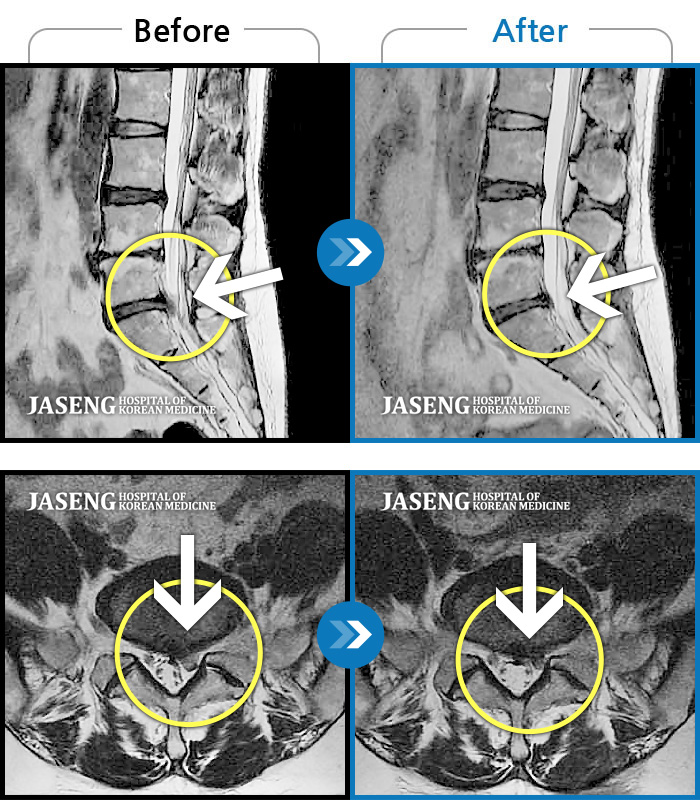

[뱸] 19.11.28~25.05.06